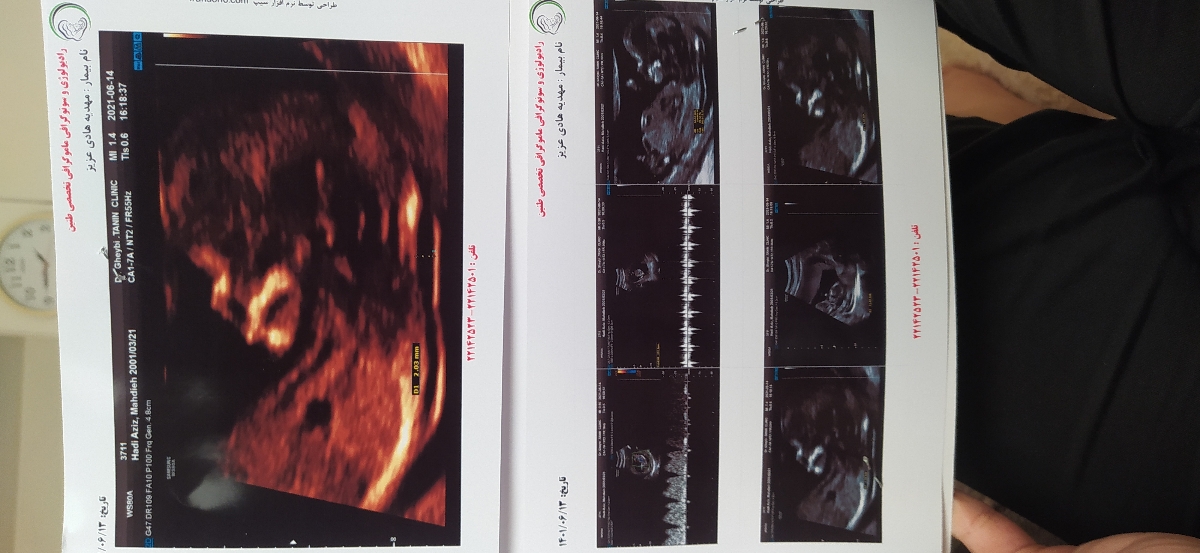

خانما من سونو گرافی ntدادم بنظرتون جنسیتش چیه خیلی ذوق دارم زود بفهمم

عکس سونوتو اگ داری بفرس

مهدیه هادی عزیز

پسر

پسره احتمال زیاد

پسرررره

پسره

سرش مثل برا من مربعی هست

دکتر سونو کردنی با اطمینان کامل نمیگه

حدس میزنن فقط